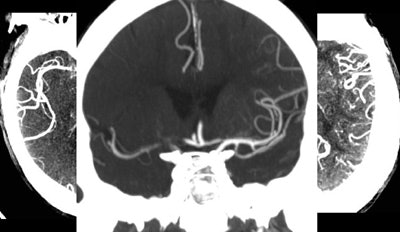

"We get an unenhanced CT, and if the patient is within three to 4.5 hours of stroke onset, they're otherwise IV-tPA eligible, and there's no bleed, they get IV-tPA," he said. It takes about eight to 10 minutes to mix up the tPA formula -- just about enough time to get a CT angiography (CTA) scan, which serves up two important pieces of information.

"It tells us if there is an occlusion in the M1 or M2 or basilar arteries that is a target for intra-arterial clot retrieval, and it also tells us about the collaterals and how the patient is likely to do if we don't treat them," Lev said.